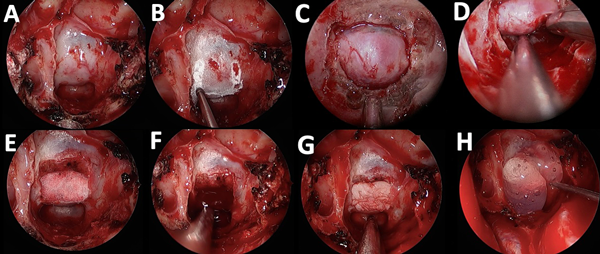

Nuestro equipo ha desarrollado una técnica endoscópica que denominamos de las “7E” (i.e.: endoscópico endonasal, exposición, extradural, elevación, egreso, encastre y exclusión). La misma consiste en la exposición de la silla turca mediante un enfoque de guanti bianchi y la reconstrucción del piso selar con material heterólogo.5,6 El paso a paso de la técnica se muestra en la Figura 2. Los puntos clave se sintetizan con las 7 “E”.

Figura 2. Caso ilustrativo con el paso a paso de la técnica de las 7 “E”. A) Primera E: Técnica endoscópica. B) Segunda E: Exposición. C) Tercera E: Extradural. D) Cuarta E: Elevación. E y F) Quinta E: Egreso. G) Sexta E: Encastre. H) Séptima E: Exclusión.

Documentación de imágenes quirúrgicas

Durante todos los casos, se utilizó un endoscopio Storz Decq® con óptica de 0° (Karl Storz SE & Co, Tuttlingen, Alemania) conectado a una cámara de endoscopía HD Stryker® 1588 AIM (Advanced Imaging Modalities) (Stryker, Michigan, EE. UU.). Los procedimientos quirúrgicos se grabaron utilizando un dispositivo de captura de video, AVerMedia ER130 EzRecorder 130® (AverMedia Technologies, Taipéi, Taiwán). Las imágenes fueron editadas en PowerPoint versión 16.79.1 (Microsoft, Nuevo México, EE. UU.).